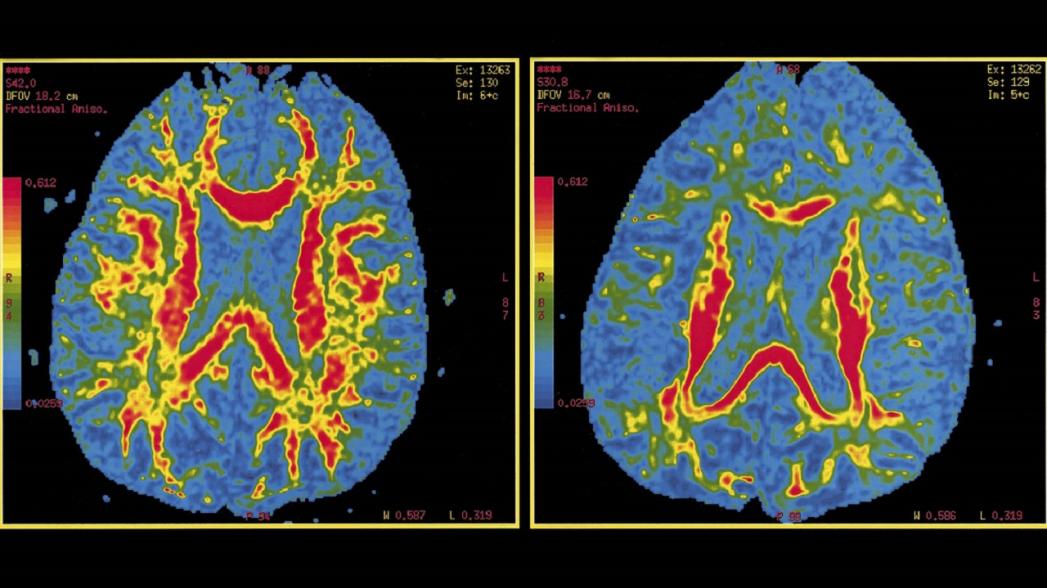

Технология была создана с использованием передовых методов распознавания изображений компании Fujifilm. С помощью AI-технологий были извлечены и рассчитаны закономерности атрофии гиппокампа и передней височной доли - областей, которые сильно коррелируют с прогрессированием болезни Альцгеймера. На основе этих моделей прогнозируется прогрессирование заболевания.